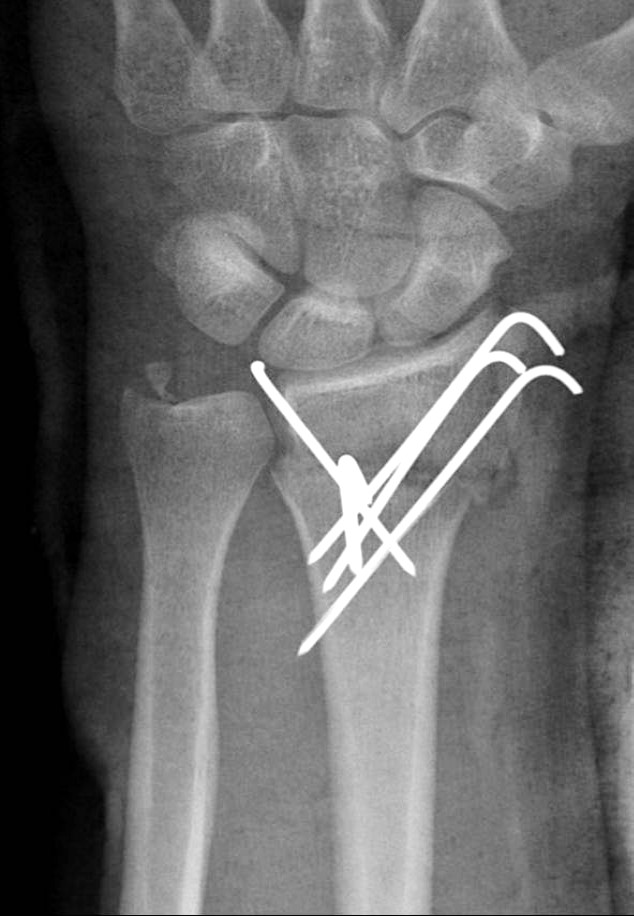

Subramanian P, Kantharuban S, Shilston S, Pearce OJ. Complications of Kirschner-wire fixation in distal radius fractures. Tech Hand Up Extrem Surg 2012;16(3):120-3.

Lakshmanan P, Dixit V, Reed MR, Sher JL. Infection rate of percutaneous Kirschner wire fixation for distal radius fractures. J Orthop Surg (Hong Kong) 2010;8(1):85-6.